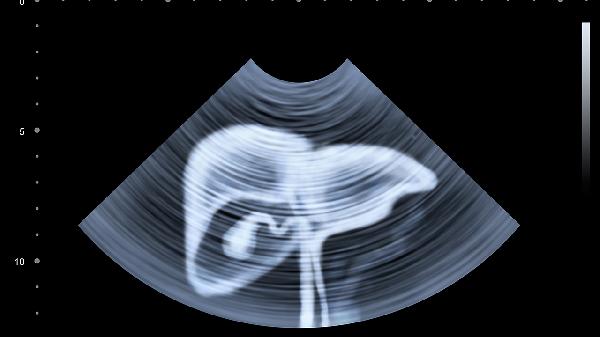

女性右侧卵巢囊肿蒂扭转或破裂会导致右下腹隐痛,可能与内分泌失调、炎症刺激相关,可能伴随月经紊乱。需通过超声检查确诊,较小囊肿可服用桂枝茯苓胶囊活血化瘀,较大囊肿需行腹腔镜囊肿剔除术。经期需避免剧烈运动,定期复查囊肿变化情况。